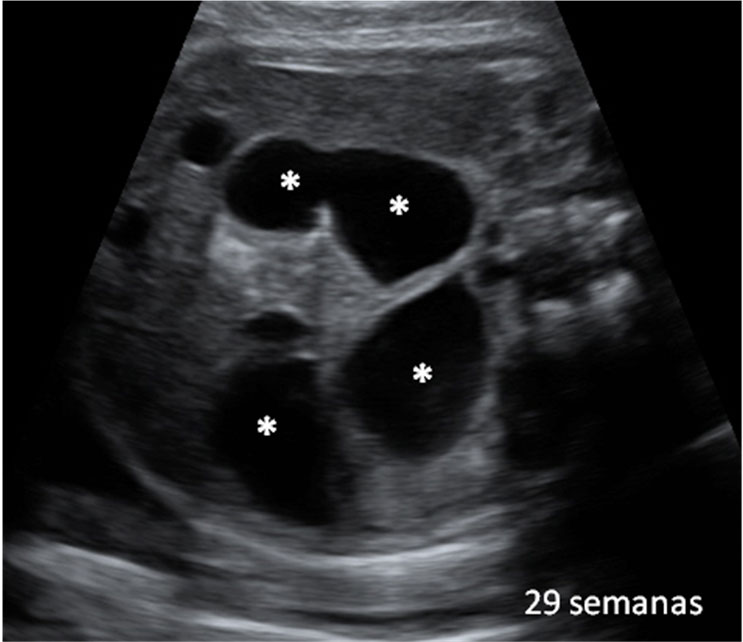

Esta ecografía 4D de la semana 20 de embarazo muestra que los bebés prácticamente empiezan a chuparse el dedo dentro del útero materno. El feto se acerca el dedo pulgar a la boca y en las imágenes finales la abre, muy probablemente para chupárselo.

En las imágenes del final, se puede apreciar cómo la criatura incluso abre la boca, quizá para chuparse el dedo pulgar. Es un reflejo el de succión que mantendrá fuera del útero, ya sea con su propio dedo o mediante la lactancia materna.